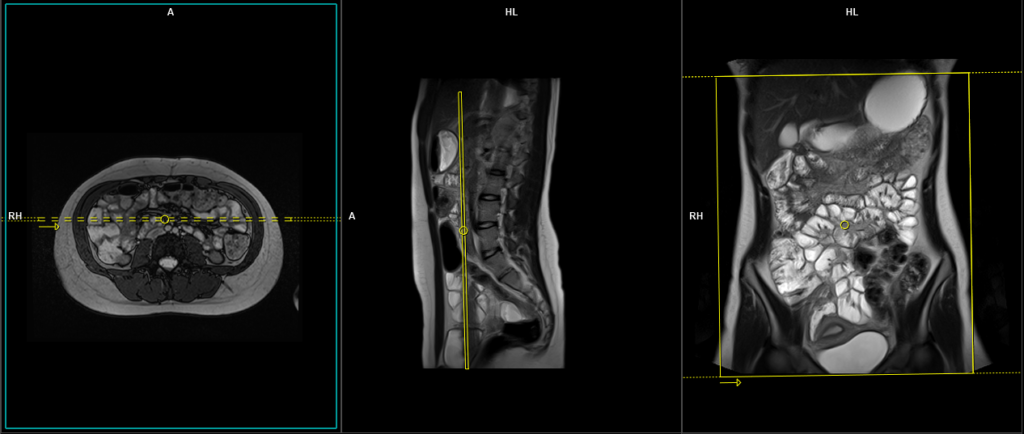

T1 VIBE DIXON \ flash fat sat 3d 0.9-1 mm coronal pre-contrast

Plan the coronal slices on the axial image. Position the block horizontally across the abdomen as shown, and ensure that the positioning block is also checked in the other two planes. Establish an appropriate angle vertically across the abdomen in the sagittal plane. Make sure the slices adequately cover the entire abdomen, extending from the anterior abdominal wall to the erector spinae muscle. The field of view (FOV) should be large enough to encompass the abdomen and pelvis, ranging from the stomach to the pubic symphysis. To prevent wrap-around artifacts, phase oversampling, and in the case of 3D blocks, slice oversampling must be used. Instruct the patient to hold their breath during image acquisition. (In our department, we instruct the patients to breathe in and out twice before giving the “breathe in and hold” instruction.)

Protocol Parameters T1 FLASH Coronal

TR 3-4 | TE 1-2 | FLIP 12 | NEX 1 | SLICE 1 MM | MATRIX 384X320 | FOV 400-450 | PHASE R>L | OVERSAMPLE 50% | IPAT OFF |